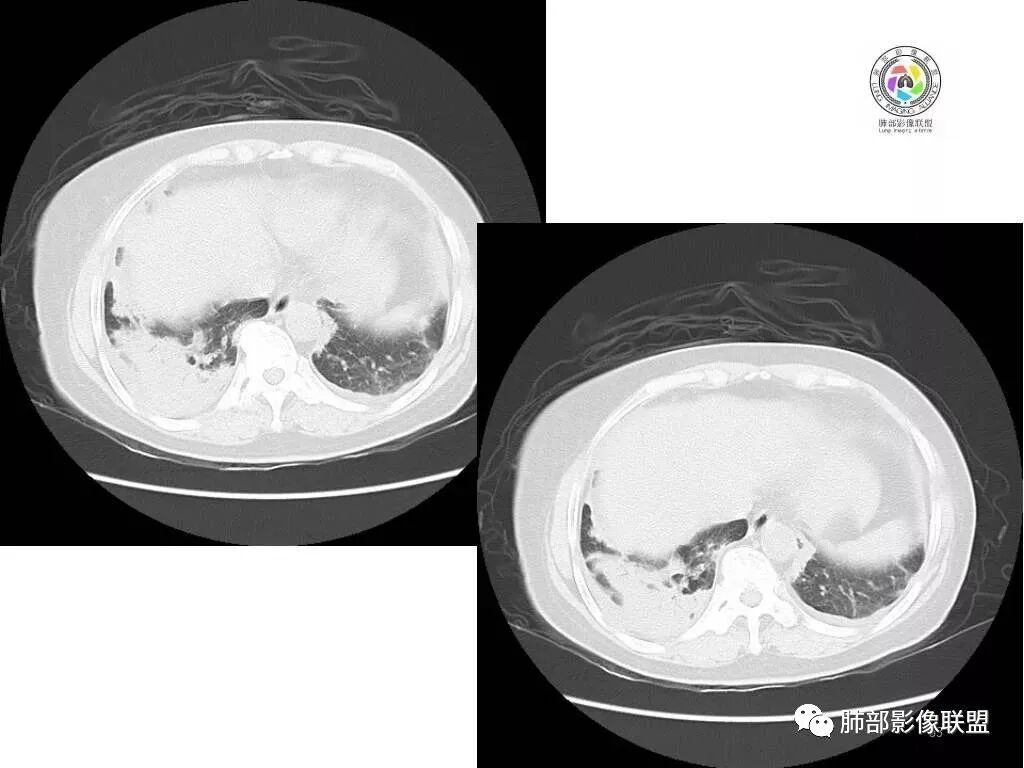

中年女性,既往类风湿,症状逍遥复查胸CT提示双肺结节较前扩大。无发热,无感染中毒症状。

胸部CT提示双肺多发的斑片实变结节影,磨玻璃。病灶分布以双肺胸膜下为主,部分病灶以支气管血管素分布,病灶内可见支气管穿行。总体符合间质性肺疾病。

荚膜抗原阴性结核阴性,肺泡灌洗液回报无特异性,无感染中毒症状以及血象异常,暂不考虑感染。

肿瘤也不符合。

考虑间质性肺疾病,机化性肺炎,

1.中年女性,发现双肺多发病变,且增多增大。

缺乏呼吸道症状及中毒症状,实验室炎性指标不高

既往多关节肿痛一年余,被诊断“类风湿”。此次就医无关节肿痛。

2.双肺多发片状影,胸膜下分布为主,部分沿支气管血管束分布,边界不清,实性及磨玻璃密度,趋于柔和,可见支气管进入或穿行,未见空洞、钙化及树芽等。部分病灶显示反晕。

3.未见腔积液。